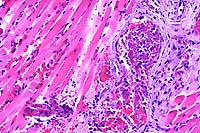

4x

obj

40x

- Case 7-1. Dermis. The 4x view demonstrates a

thrombus within a valved vein (left of center). The dermal connective

tissue is expanded by hemorrhage beneath the epidermis and around

blood vessels. The 40x view shows the thrombus and vessel wall

in which there are vague outlines of bacilli.